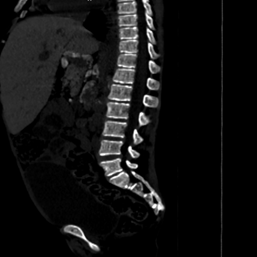

Fig 2(a) Fig 2(b)

Figure 2(a): Non

contrast CT abdomen axial image showing hepatomegaly with left lobe

enlargement, extending to the left hypochondrium (beaver tail variant), 2(b): Non contrast axial

image of the abdomen showing a distended gall bladder containing a 7 mm

hyperdense calculus (arrow)

Figure

3(a,b): Bone window

CT images of the abdomen in the sagittal and coronal plane window showing

coarse trabeculations in the axial skeleton

The visualized axial

skeleton demonstrated coarsened trabeculae characteristic of thalassemic bone

changes, with no paravertebral masses identified (Figure 2).

Skeletal manifestations

The

coarsened trabecular pattern observed on CT represents the skeletal response to

chronic anemia and extramedullary hematopoiesis. Marrow expansion led to

cortical thinning and altered trabecular architecture, predisposing patients to

pathological fractures10,16.